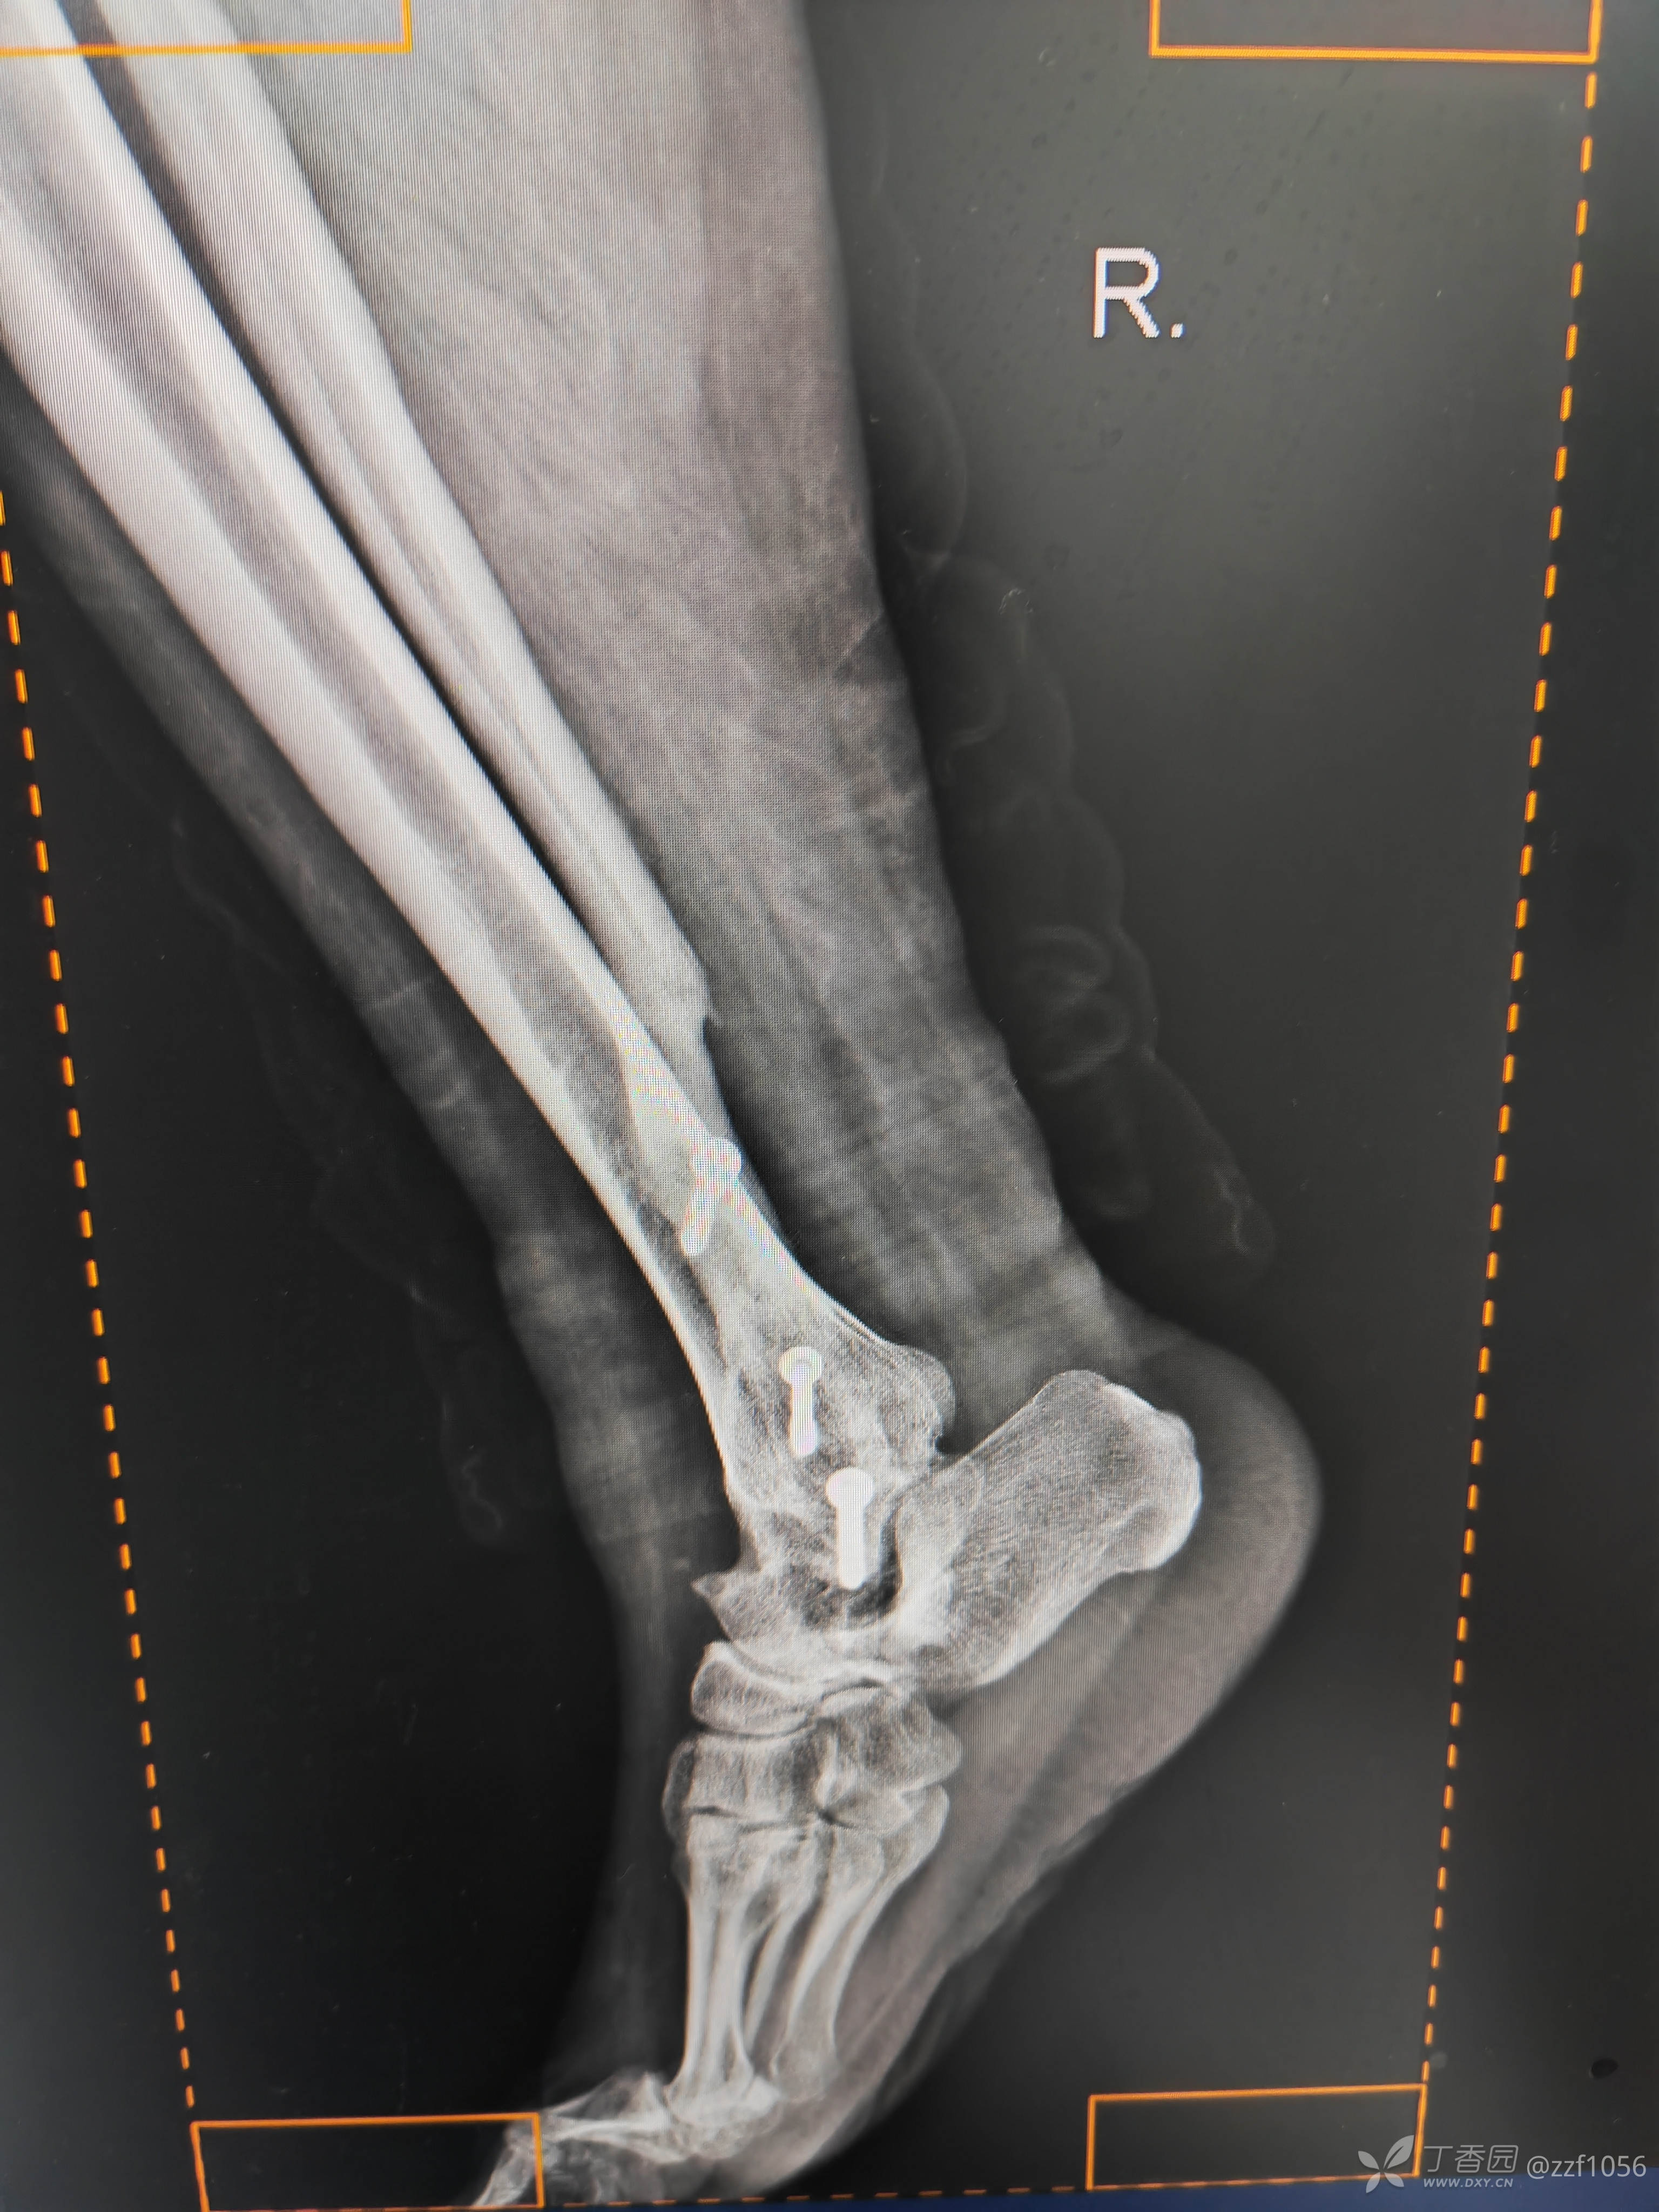

术后

就备了一块融合钢板,偏长了点

应该是90°➕

总体满意